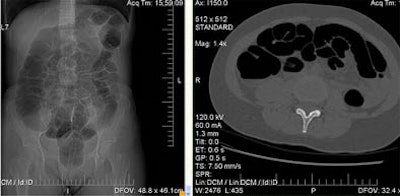

| A 65-year-old woman underwent follow-up VC following a right colectomy for colon cancer. The intervention three years earlier included removal of the ileocecal valve with subsequent ileocolic anastomosis. Insufflation in the supine decubitus did not cause abdominal pain. At VC the colon was normal but shows overdistension of the small bowel in the supine CT data (above) and confirmed in the prone CT data (below). Objective or subjective symptoms were not reported. Immediately after prone decubitus positioning, at the end of the exam, the patient reported headache, nausea, and stimulus to vomiting. Cold sweat and diaphoresis were also observed. All images courtesy of Dr. Emanuele Neri. |